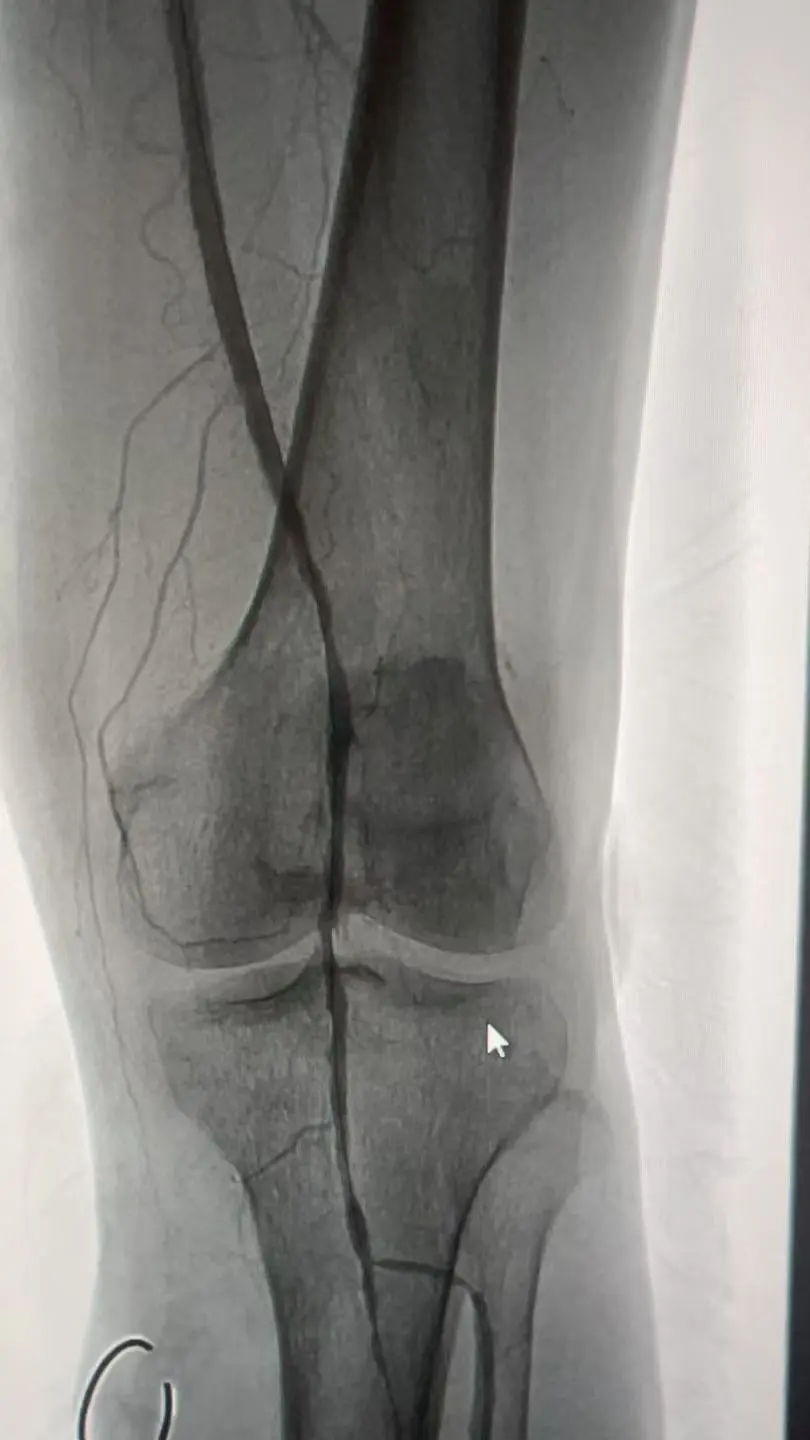

手术在DSA室精准开展:团队以C臂及影像学检查定位腰2-3交感神经节,避开周围脏器血管,将射频消融针置入目标区域,在安全温度下完成神经消融;随后经股动脉穿刺建立通路,导丝顺利通过闭塞段,采用长球囊低压扩张重建血管管腔。术中造影显示,闭塞血管成功开通,血流直达足部,患者即时感觉疼痛缓解,足背皮温升高。

整个手术历时90分钟,无出血、血管穿孔等并发症。术后患者疼痛评分由术前9分降至2分,当晚即可安睡,皮肤颜色恢复红润。肢体功能完全恢复,成功避免截肢。